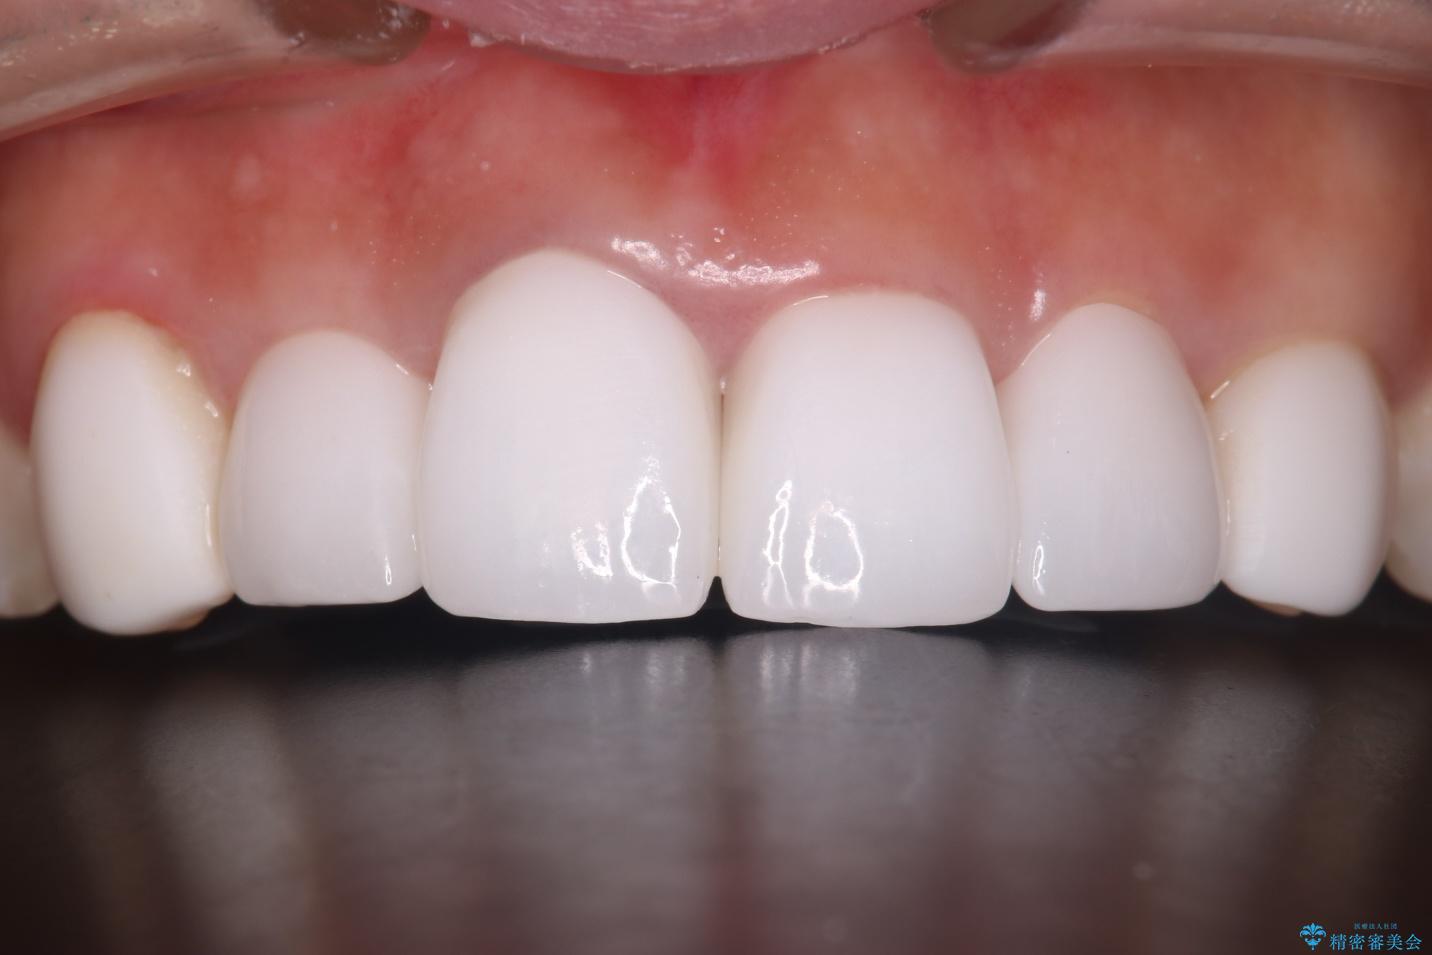

- 他院で治療した前歯の色が気になるということで来院された患者様です。前歯に色の差があり、レントゲンから内部にう蝕も見られたため、審美性に優れ、う蝕になりにくいオールセラミッククラウンで治療いたしました。

清掃性も上がったおかげで、歯肉の状態も良好に保てています。

色の調和もとれたので非常に満足いただけました。